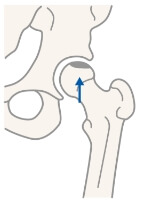

大腿骨寛骨臼インピンジメント

大腿骨寛骨臼インピンジメントは寛骨臼側、大腿骨側における軽度の形態異常によって、股関節運動時に繰り返しインピンジメント(衝突)が生じることにより、寛骨臼縁の関節唇および軟骨に損傷が惹起される病態とされます。スポーツ障害の一因としても注目されています。寛骨臼縁あるいは大腿骨頭頚部移行部の特徴的な画像所見のみでなく、臨床所見も含めて評価する必要があります。

大腿骨側の軽度の形態異常Cam type

寛骨臼側の軽度の形態異常Pincer type

大腿骨側と寛骨臼側の軽度の形態異常Combined type